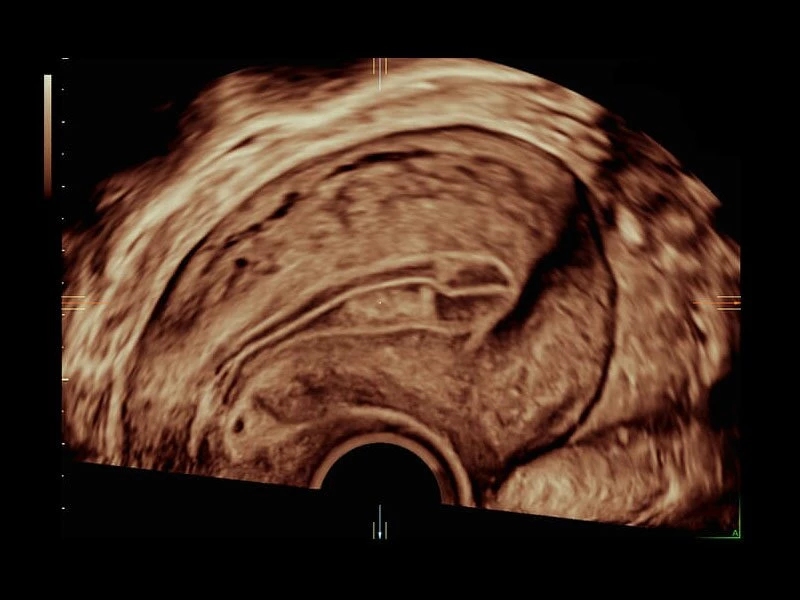

Четкие и подробные изображения

В медицинском учреждении, которое работает в условиях высокой нагрузки, значение имеет каждая минута. У врача нет времени подолгу корректировать параметры настройки, чтобы добиться наилучшей детализации изображения. Инновационная архитектура УЗИ аппарата Voluson E10 избавляет вас от лишних хлопот, — вы сразу получаете безукоризненную картинку. Вам не придется тратить лишнее время и силы: качество визуализации безупречно в любом режиме — от двумерных изображений до новейших 3D/4D технологий.

Современные клинические приложения и высокое качество изображений позволяют использовать Voluson E10 для наблюдения за ходом беременности максимально эффективно. С помощью этого аппарата можно проводить любые исследования, как рутинные, так и комплексные, выявляя проблемы на ранних стадиях и принимая своевременные меры.

Объемное сканирование Voluson — 3D/4D вашей мечты

Объемное УЗИ на Voluson E10 — это не просто потрясающе красивая картинка, это ценный инструмент получения дополнительной информации при обследовании женщин.

Инновационная технология визуализации HDlive обеспечивает получение реалистических изображений за счет эффекта объемного зрения, повышая достоверность клинической оценки. Теперь режим HDlive дополняют две новые функции:

- Технология HDlive Silhouette — задает разный уровень прозрачности, помогая выявлять контуры внутренних структур и точнее оценивать состояние плода в первом триместре.